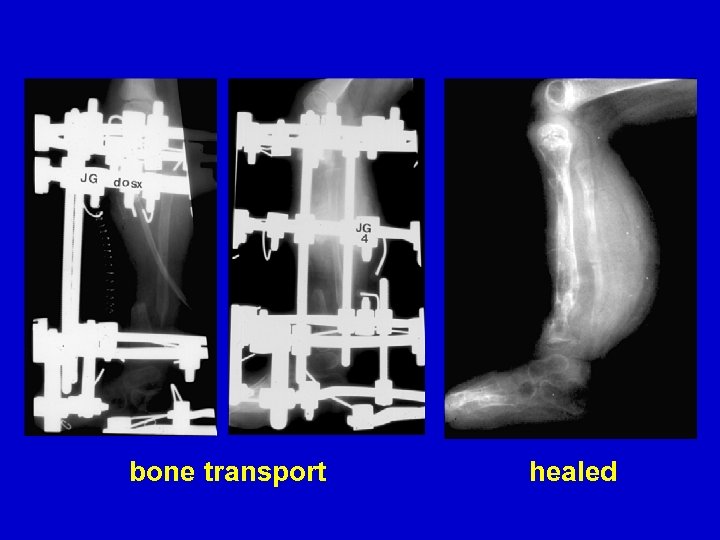

Type II Treatment Bone transport Acute shortening

CPT resection

acute shortening re-lengthening

bone transport healed